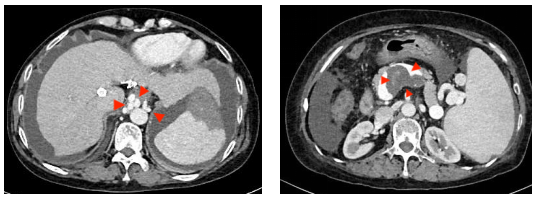

但在一周前, XX女士再次感到腹胀难忍、黑便重现,随即来到市四医院消化内科就诊。医务人员检查发现她存在大量腹水、食管胃底静脉曲张和门静脉血栓——虽然彩超显示原TIPS支架内血流通畅,但结合其病史,医务人员判断:原分流道分流量不足,导致门静脉高压问题没有真正得到解决

手术中,在兄弟科室的全力配合下,介入团队精准测量发现何女士门静脉压力梯度高达26mmHg,证实原通道分流量严重不足。随后,医务人员经肝右静脉成功穿刺门静脉右支,在栓塞严重曲张的静脉后,建立了一条全新的8mm分流道。